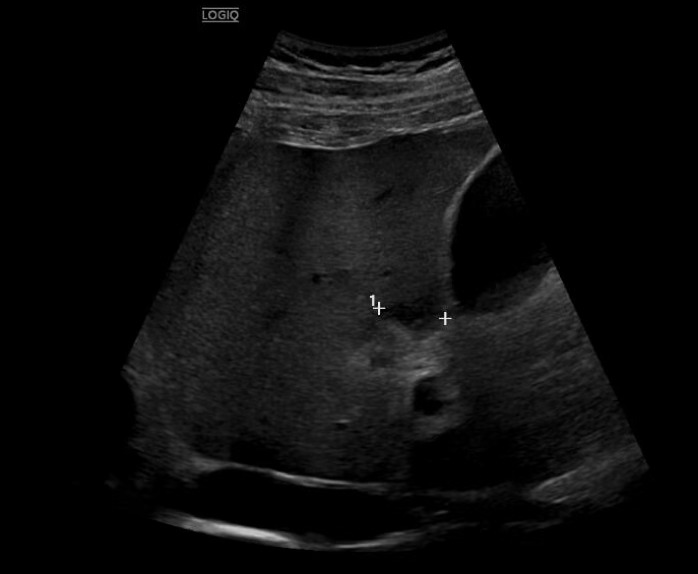

La ecografía abdominal urgente muestra engrosamiento parietal del colon descendente-sigma-recto, aumento de ecogenicidad de la grasa pericólica e hiperemia, compatibles con colitis izquierda.

Se realiza tomografía computarizada abdominal con contraste, identificando un absceso pericólico de 2,8×5,7 cm en sigma, cambios inflamatorios mesentéricos y signos sugestivos de pileflebitis.